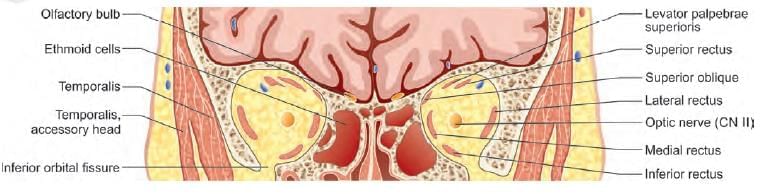

A patient presented with squint in right eye, as shown below. Identify the nerve lesioned in this case: (NEET-PG 2020p)

A child presented with left sided head tilt. On head straightening, there is right hypotropia, which increases on tilting head to right side. Which of the following muscle is paralysed? (AIIMS June 2020)